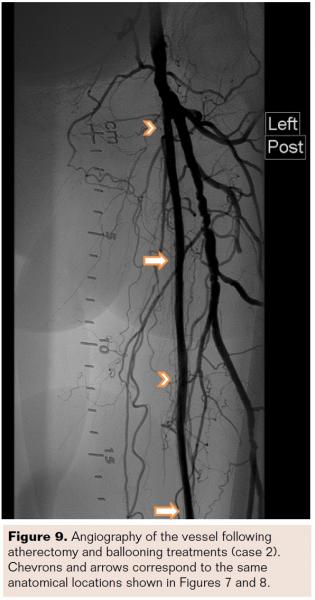

After an appropriately sized lumen was created, the TE was removed and the TT inserted to the proximal edge of the lesion. The laser was again set to 45 fluence at 25 Hz. Five passes were made with the TT to satisfactorily debulk the lesion and prepare it for PTA (Figure 8). The catheter was rotated after each pass in order to remove as much material as possible. Angioplasty was then performed in a step-wise fashion, using three inflations along the length of the lesion, working from proximal to distal. Inflations were between 6 atm and 10 atm for 2 minutes to 3 minutes with a 5 mm x 200 mm balloon. The result was a reduction of the ISR from 100% to 23% diameter stenosis. The procedure was successful with no adverse device-related events (Figure 9). This patient was followed for 12 months without the need for revascularization.